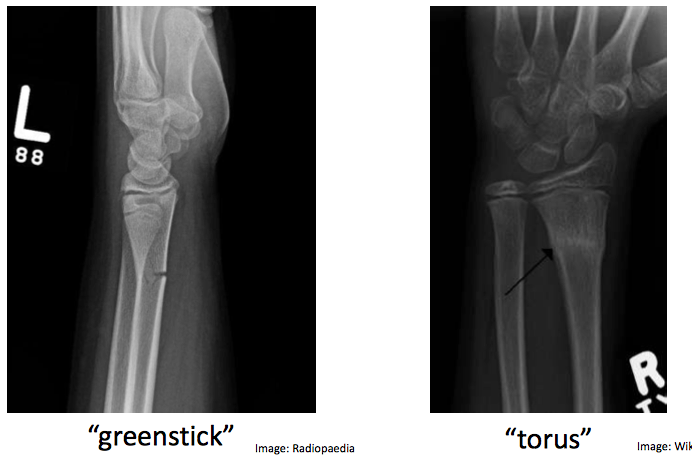

Describe the difference between a complete and incomplete fracture?

Complete: break all of cortex

Incomplete: just break one side of cortex